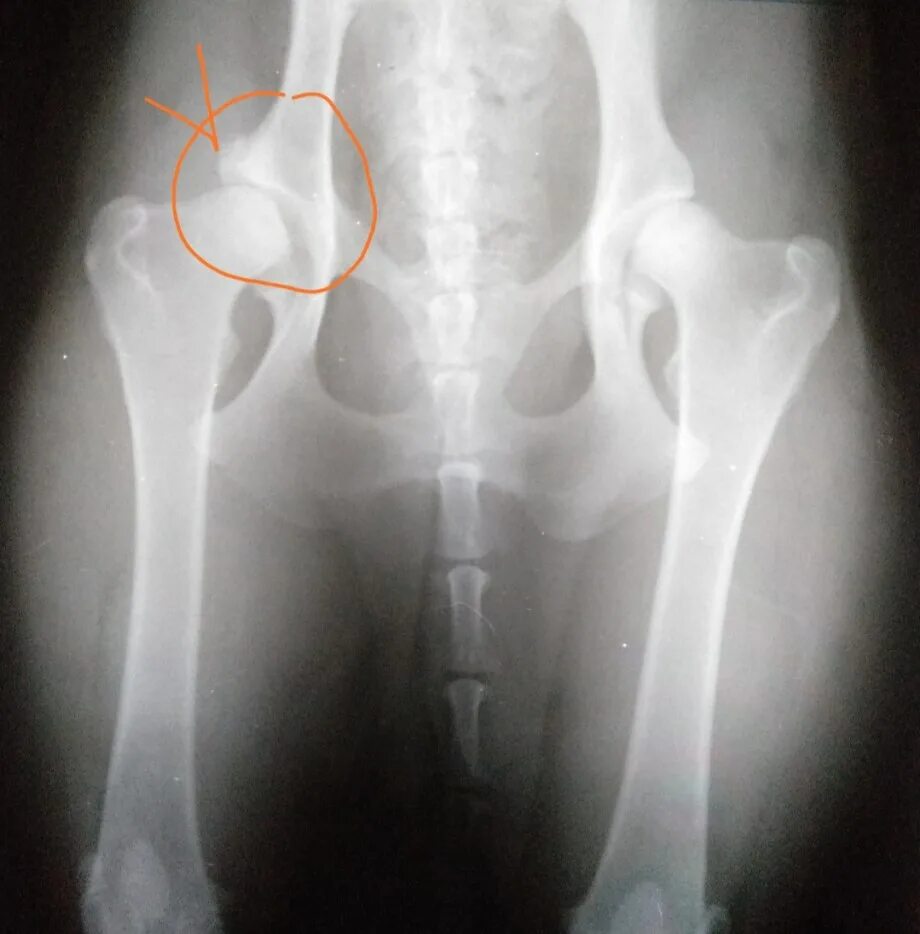

Дисплазия 7 лет